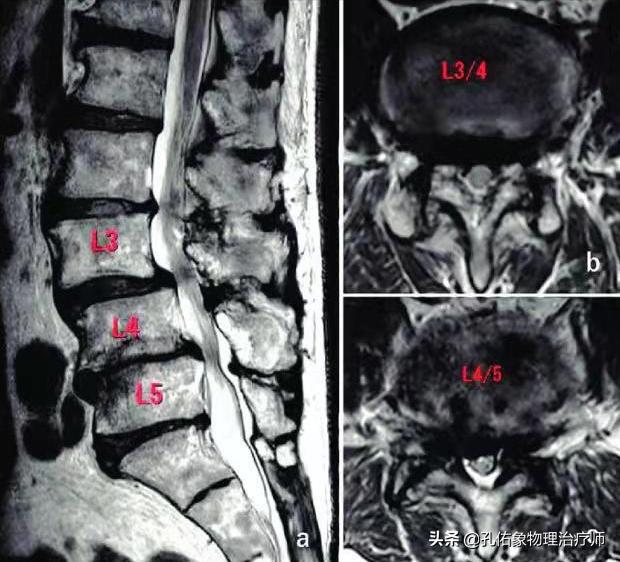

如上圖中所示,椎管在椎間盤(髓核+纖維環(huán))的后方,里面穿行脊髓;若是因?yàn)槟撤N因素使椎管變窄了,很可能會壓迫神經(jīng)、脊髓等。

常見導(dǎo)致椎管狹窄的因素主要有:

腰椎的椎體后緣增生,后縱韌帶的鈣化,小關(guān)節(jié)突增生,側(cè)隱窩狹窄,黃韌帶肥厚,椎管內(nèi)占位(腫瘤或間盤脫出)。